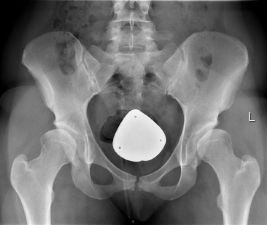

Hip dysplasia is a condition in which the acetabulum (hip socket) does not fully develop from birth or after a growth spurt in adolescence or young adulthood (Pun, 2016). This means that the acetabulum is shallow or does not form a proper weight bearing surface over the femoral head. Congenital cases are usually referred to as Developmental Dysplasia of the Hip (DDH) whereas cases in adolescents and young adults are referred to as Adolescent onset or Acetabular Dysplasia.

The abnormal biomechanics of hip dysplasia can lead to the onset of secondary hip osteoarthritis at a much earlier age than usual, ultimately requiring a hip replacement at an early age (Wyles et al, 2017). Pelvic Osteotomy (also called Periacetabular Osteotomy or PAO) is a surgery that reshapes the acetabulum to better cover the femoral head, aiming to delay the onset of OA and therefore delay THR (Coobs et al, 2015). There is some evidence showing good survival rate in PAOs at 20 years (Steppacher et al, 2008). Some can even get back into impact sports, some can’t or may choose lower-impact activities.